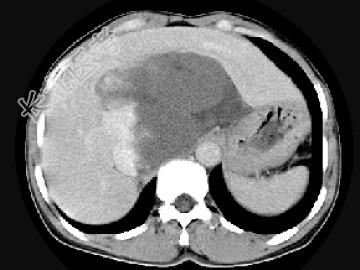

- 单项选择题女,48岁, 中上腹不适,CT扫描如图, 最可能的诊断为 ( )

A、原发性肝癌

B、胆管细胞癌

C、肝血管内皮瘤

D、肝血管瘤

E、小肠间质瘤